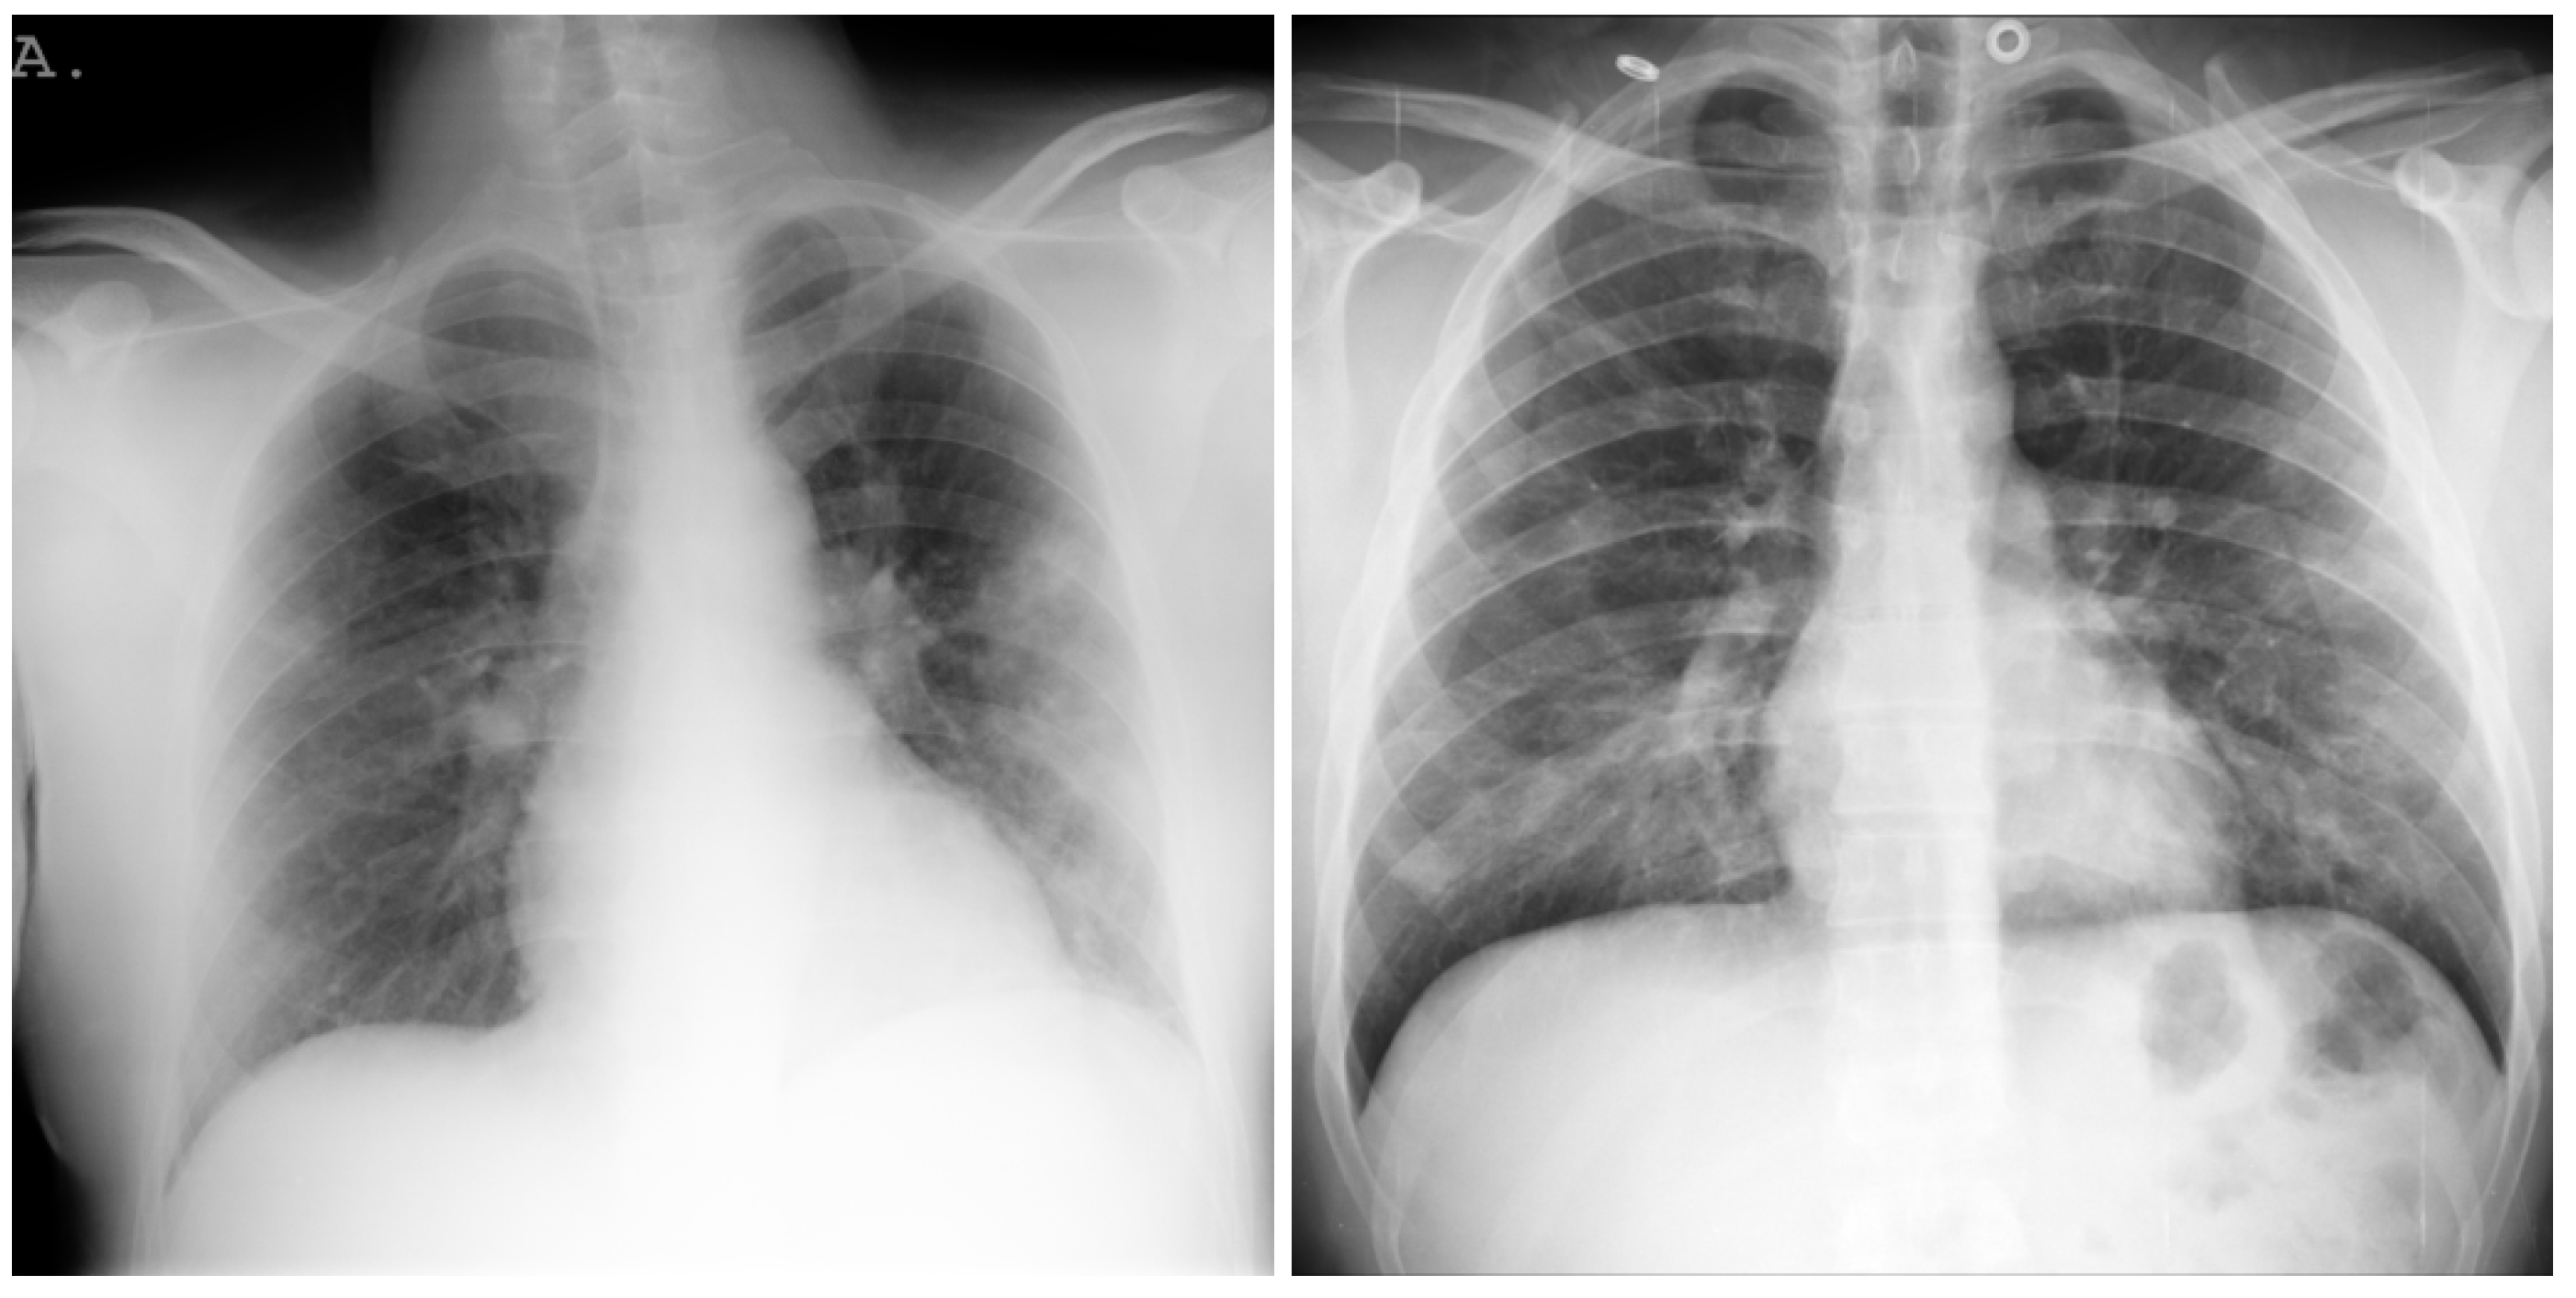

3.9. Montfort Dataset

5. Individual Tests

5.1. DeepCCXR-Bin for Individual Datasets